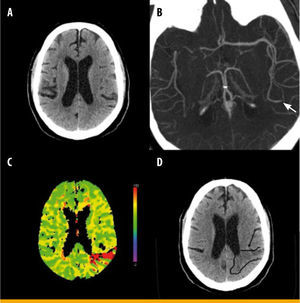

Imagen funcional en el ictus isquémico agudo. Tomografía computarizada (TC) craneal con estudio de perfusión en un paciente de 57 años con diabetes, con un ictus isquémico agudo en el hemisferio izquierdo tratado con fibrinolisis intravenosa, que presentaba una glucemia al ingreso de 256mg/dL. La TC craneal basal no aprecia alteraciones relevantes (A), en la angio-TC se observa oclusión arterial de una subdivisión de la arteria cerebral media izquierda (flecha verde en la imagen B), y el estudio de perfusión muestra un área de isquemia irreversible y penumbra circundante en la región parietooccipital izquierda (en rojo en la imagen C). En la TC craneal de control realizada a las 24 horas se observa un infarto agudo en la región alterada previamente en la TC de perfusión (flecha y contorno negro en D)

Con respecto a la trombolisis intravenosa, ésta ha demostrado sus beneficios si se aplica en las primeras cuatro horas y media desde el inicio del ictus, debido a la disminución de las tasas de discapacidad, sin aumento de la mortalidad a pesar de un moderado incremento de las complicaciones hemorrágicas en los pacientes tratados con este fármaco. La hiperglucemia en el ingreso >140mg/dL se asocia a peor pronóstico en los pacientes que reciben rtPA, sobre todo si se produce una recanalización precoz, favoreciéndose en este caso el daño por reperfusión. La hiperglucemia se ha mostrado como un elemento que puede distorsionar el funcionamiento de la fibrinolisis intravenosa (figura 2).

En un trabajo realizado para evaluar si las cifras altas de glucemia influían en las tasas de recanalización de los pacientes fibrinolisados, se observó que aquellos con hiperglucemia al ingreso >158mg/dL presentaban un menor porcentaje de recanalizaciones (16 frente a 36,1%). Sin embargo, no se encontró correlación estadística con las cifras elevadas de hemoglobina glucosilada, lo que indica que la hiperglucemia aguda, y no el estado de hiperglucemia crónica, condicionaba estos efectos desfavorables. La explicación fisiopatológica se relaciona con la capacidad de la hiperglucemia para inhibir la fibrinolisis, al ser capaz de elevar los niveles del inhibidor del activador del plasminógeno tipo 1 (PAI-1) y, a su vez, ocasionar la glicación de proteínas clave para la buena efectividad del fibrinolítico, como es el caso de la anexina II, un receptor de la superficie celular que facilita la acción de la plasmina15.